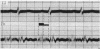

HEART MURMURS PART I

. 1947 Jan;9(1):1–15. doi: 10.1136/hrt.9.1.1